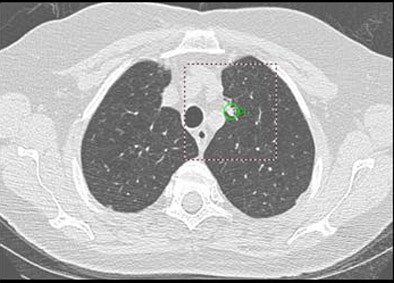

| Above: A 7-mm nodule in right middle lobe, representing a true-positive CAD finding. Below: A 5-mm nodule in the lower right lobe, representing a true-positive CAD finding. |